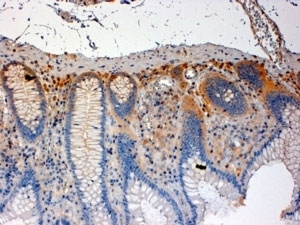

IHC staining of FFPE human colon with CSK antibody at 4ug/ml. HIER: steamed with pH6 citrate buffer, HRP-staining.